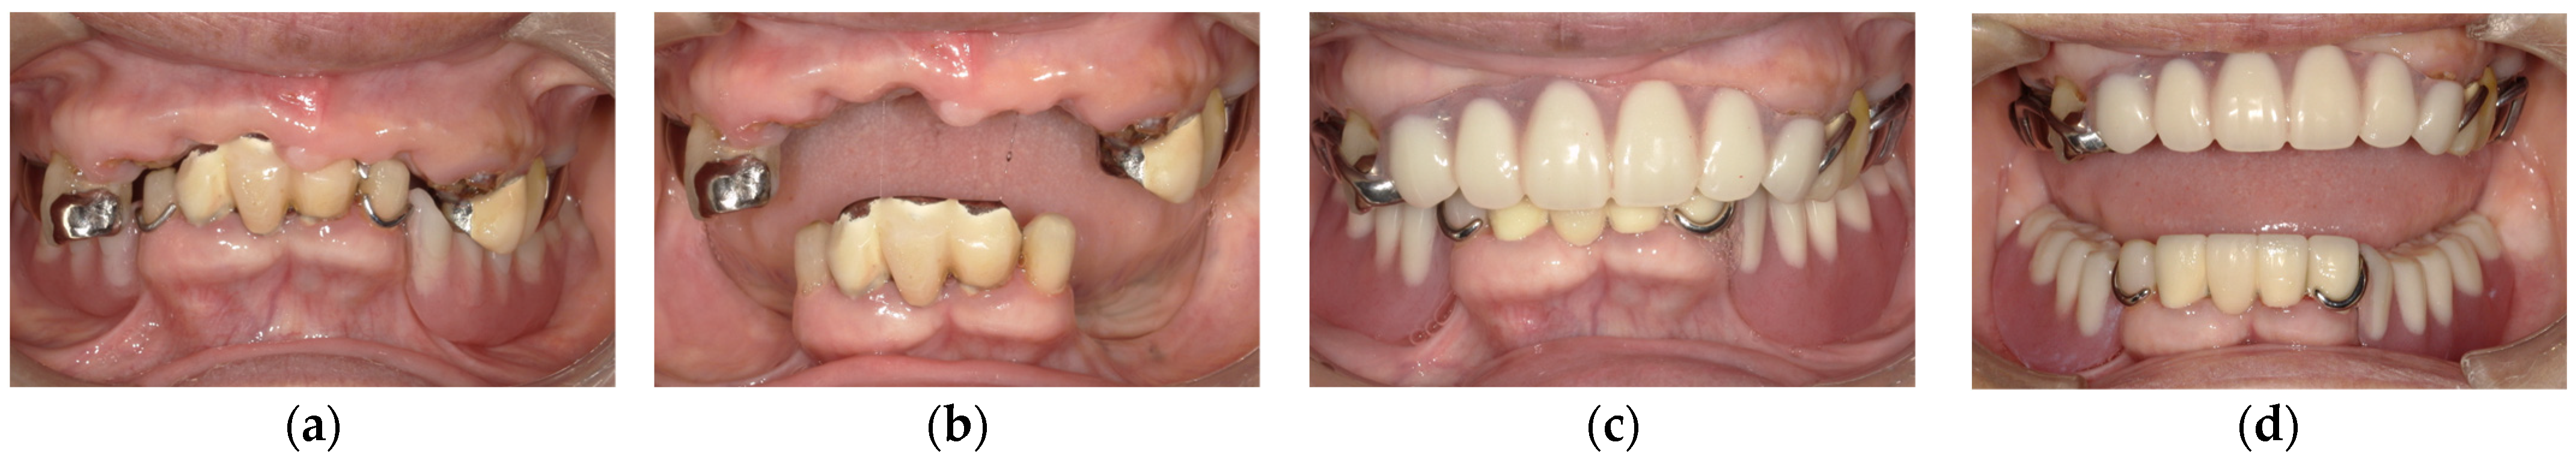

In clinical cases, anterior hyperfunction is also occasionally observed in patients classified as Eichner B4 (only anterior occlusal contacts), meaning the patients with anterior teeth in both jaws and without any posterior occlusal supports. In Eichner B4 patients, the effects of anterior hyperfunction on maxillary anterior teeth are as follows (Figure 1):

• Decay of tooth crowns;

• Mobile or flared maxillary anterior teeth;

• Troubles of prostheses in maxillary anterior teeth.

Decay of tooth crowns is attributed to anterior hyperfunction or excessive occlusal force. In addition, a loss of posterior supports and loss of VDO also may be associated. However, in our clinical cases, these teeth tended to have comparatively healthy periodontium. On the contrary, mobile or flared maxillary anterior teeth are attributed to impaired periodontium in addition to occlusal force or anterior hyperfunction. Troubles with prostheses in maxillary anterior teeth including tipping of facing materials and crown detachment occur due to excessive occlusal force and sequential cement wash-out. In addition, excessive occlusal force may result in tooth fracture. Secondary caries following cement wash-out and/or abutment tooth fracture may be associated with crown detachment.

Figure 1. The effects of anterior hyperfunction on maxillary anterior teeth: (a) decay of tooth crowns; (b) mobile or flared maxillary anterior teeth; (c) troubles of prostheses in maxillary anterior teeth. Source: the authors.